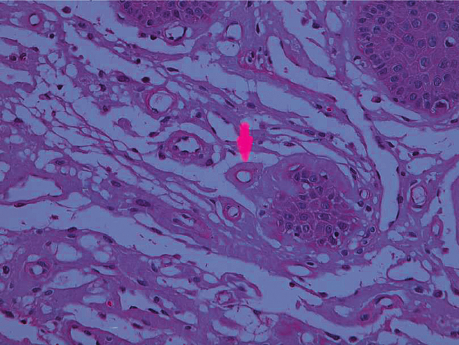

Dermoscopy And Clinicohistopathological Profile of Lichen Planopilaris Restricted To The Face: A Case Series Of Six Unusual Cases